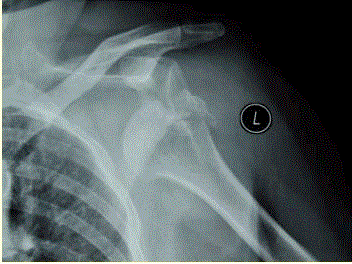

问题 患者女,58岁,左肩关节外伤,医院就诊,行X线检查,如下图。 急诊应尽快进行的处理方法是

选项 A、血常规检查 B、静脉补液 C、心电图 D、悬吊制动 E、闭合复位治疗 F、给予适当的麻醉

答案 EF